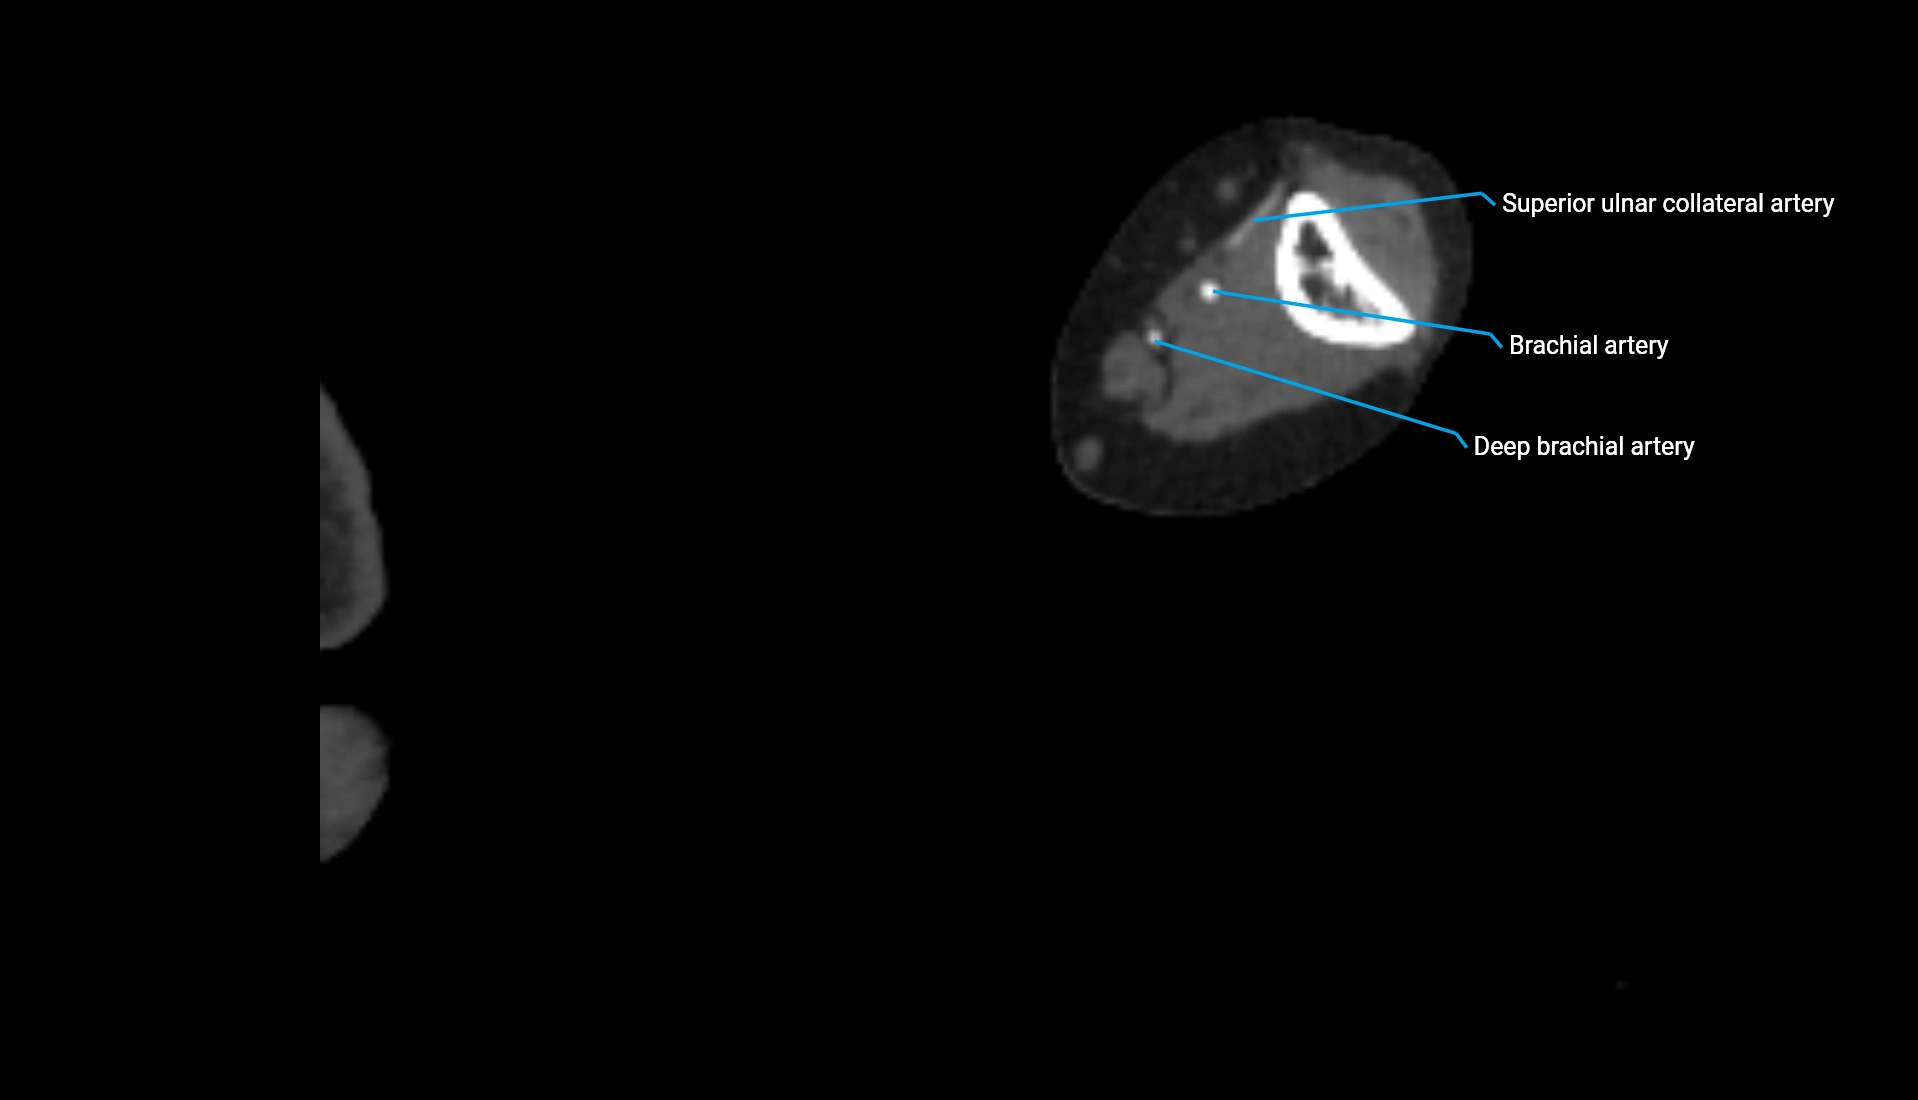

CT Appearance

Non-Contrast CT:

• Cortex: High-density, sharply defined

• Subchondral bone: Dense cancellous matrix

• Articular surface: Smooth concave contour articulating with the capitellum

• Excellent for evaluating bone integrity, alignment, and subtle fractures